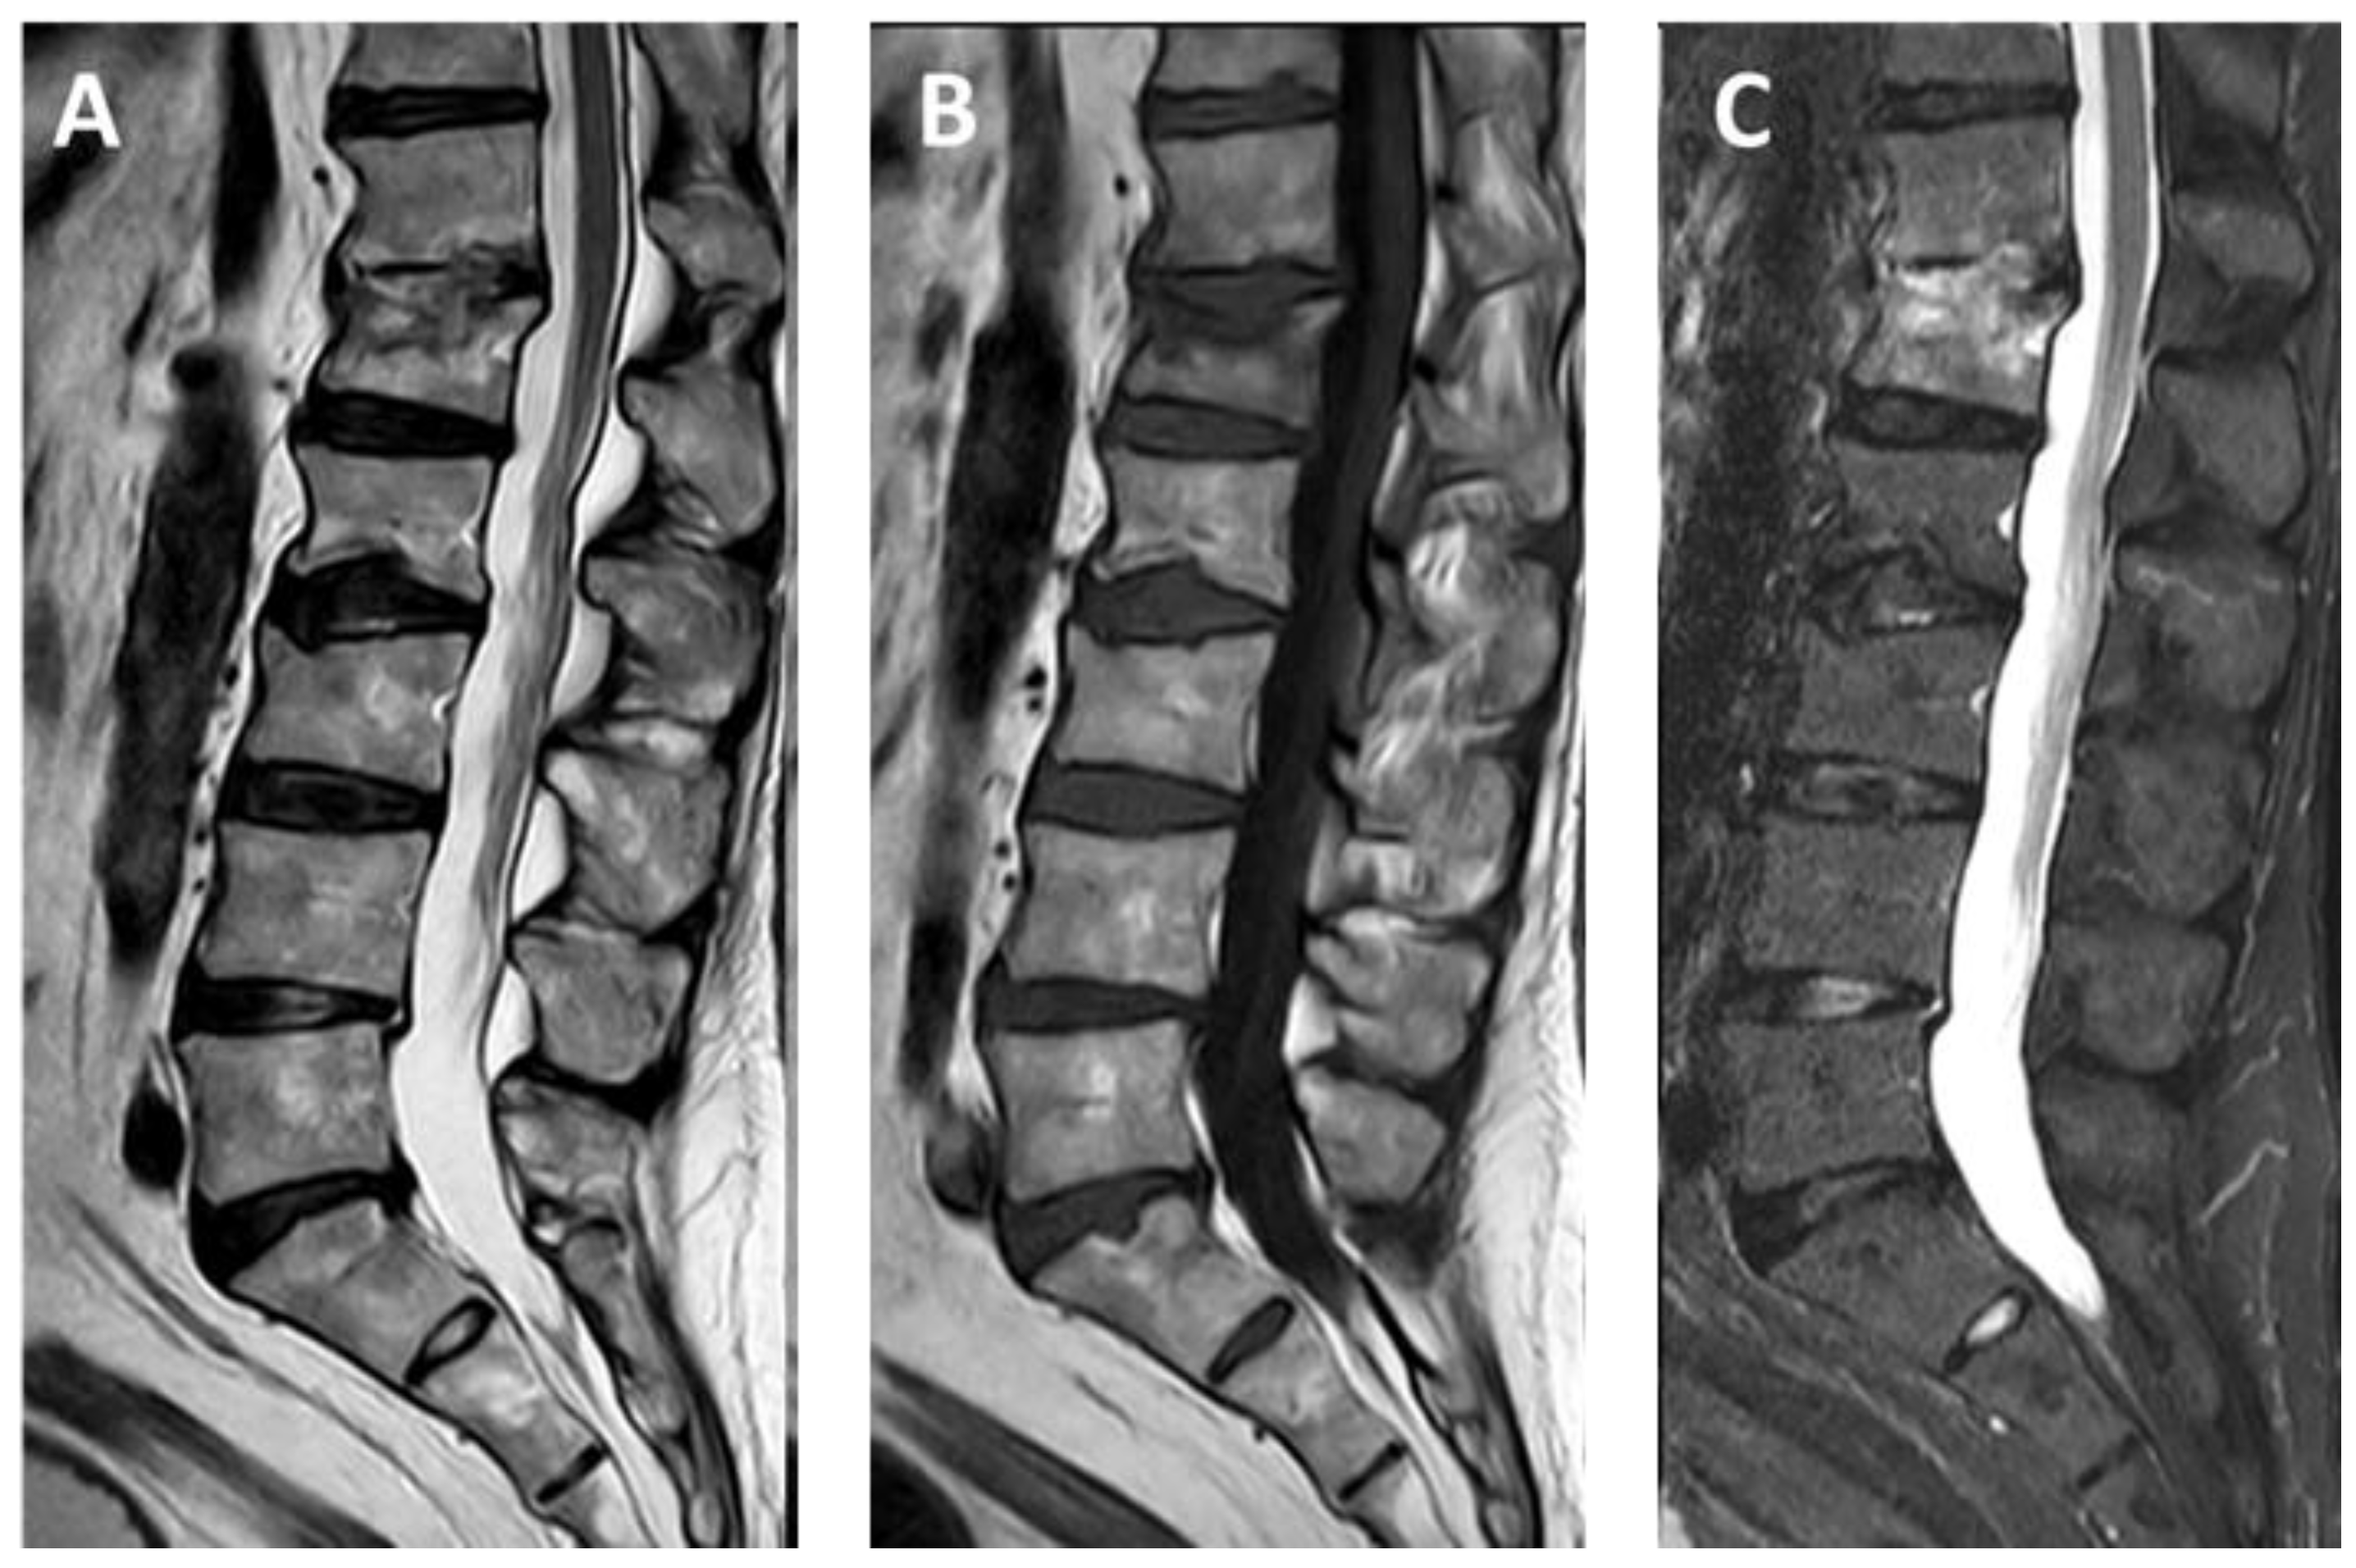

- Pusceddu, C.; Faiella, E.; Derudas, D.; Ballicu, N.; Melis, L.; Zedda, S.; Marsico, S. Re-expansion of vertebral compression fractures in patients with multiple myeloma with percutaneous vertebroplasty using spinejack implants: A preliminary and retrospective study. Front. Surg. 2023, 10, 1121981. [Google Scholar] [CrossRef]

- Pusceddu, C.; Marsico, S.; Derudas, D.; Ballicu, N.; Melis, L.; Zedda, S.; de Felice, C.; Calabrese, A.; De Francesco, D.; Venturini, M.; et al. Percutaneous Vertebral Reconstruction (PVR) Technique of Pathological Compression Fractures: An Innovative Combined Treatment of Microwave Ablation, Bilateral Expandable Titanium SpineJack Implants Followed by Vertebroplasty. J. Clin. Med. 2023, 12, 4178. [Google Scholar] [CrossRef]